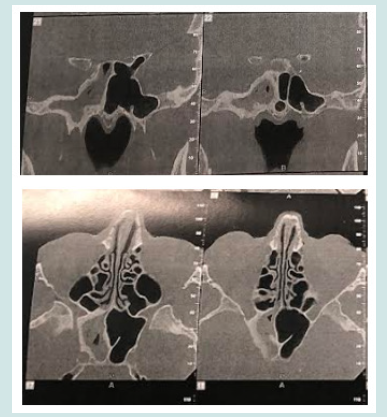

This is a 72-year-old patient, who for several years had chronic headaches, most often on the right, associated with posterior purulent rhinorrhea. The sinus CT scan showed an opacity of the right sphenoid sinus suggestive of aspergillosis (Figure 1). The patient benefited from endoscopic sphenoidotmia with evacuation of purulent intrasinus contents and excision of the pathological mucosa (Figure 2). The pathological study confirms the diagnosis of aspergillosis. The postoperative results were good.

As for ophthalmological signs, mainly explained by orbital extension and cavernous sinus invasion, they are often observed in association with invasive forms [2,3]. They are reported to be the second most common complex symptom in sphenoid diseases. The patients may complain from diplopia often subjective or more commonly secondary to ophthalmoplegia due to multiple nerve palsy [9]. Ptosis was reported in up to 46 % of published cases [10], exophthalmos, ophthalmoplegia or loss of visual acuity ranging from mild to total blindness [8]. The rhinological signs are dominated by anterior and/or posterior purulent rhinorrhea and nasal obstruction, which are very nonspecific. However blood-streaked nasal discharge to be much more specific [1]. Irritation of the sinus mucosa by the aspergilloma or, at a more advanced stage, bone destruction of the sinus wall can explain this bleeding [1]. Radiologically, the standard images appear normal they are currently neglected in terms of invasive sinusitis [2]. Indeed CT scan and MRI represent the most sensitive diagnostic means to highlight an Aspergillus sinusitis by demonstrating ferromagnetic substances [10]. Actually, CT scan is known to be more specific in detecting bone lesions [11]. The most characteristic aspect is the presence of a total filling of the sinus by dense, non-raising material after injection of iodine and comprising a calcium or metal density image corresponding to calcium salts and other heavy metals (lead, copper, iron, manganese) produced by mycosis [2,7].